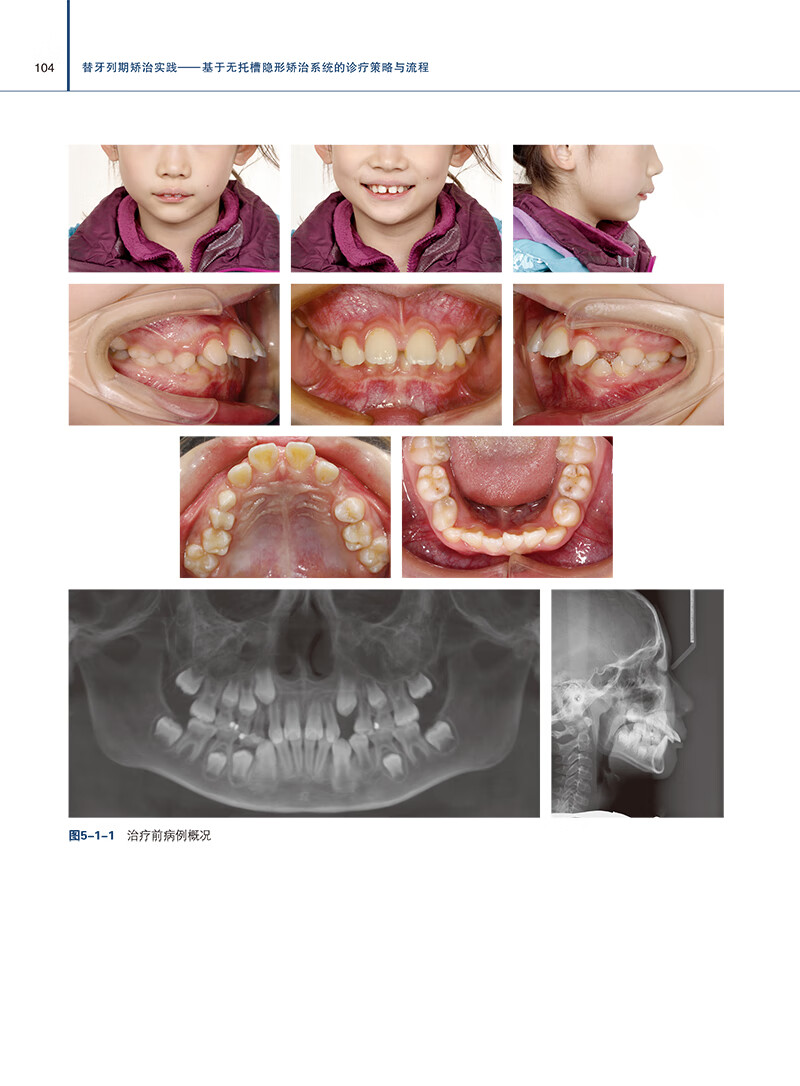

本書是一本專注於無托槽隱形矯治科技的權威著作。 書中彙集前沿隱形矯治策略與臨床實踐,深度解析替牙列期錯畸形的診療流程。 通過豐富的病例分析,揭示生長發育規律,提供科學、精准的治療指導。 本書以實戰為導向,為口腔正畸醫生提供即學即用的知識寶庫,是提升臨床技能、優化患者治療效果的必備參考書。